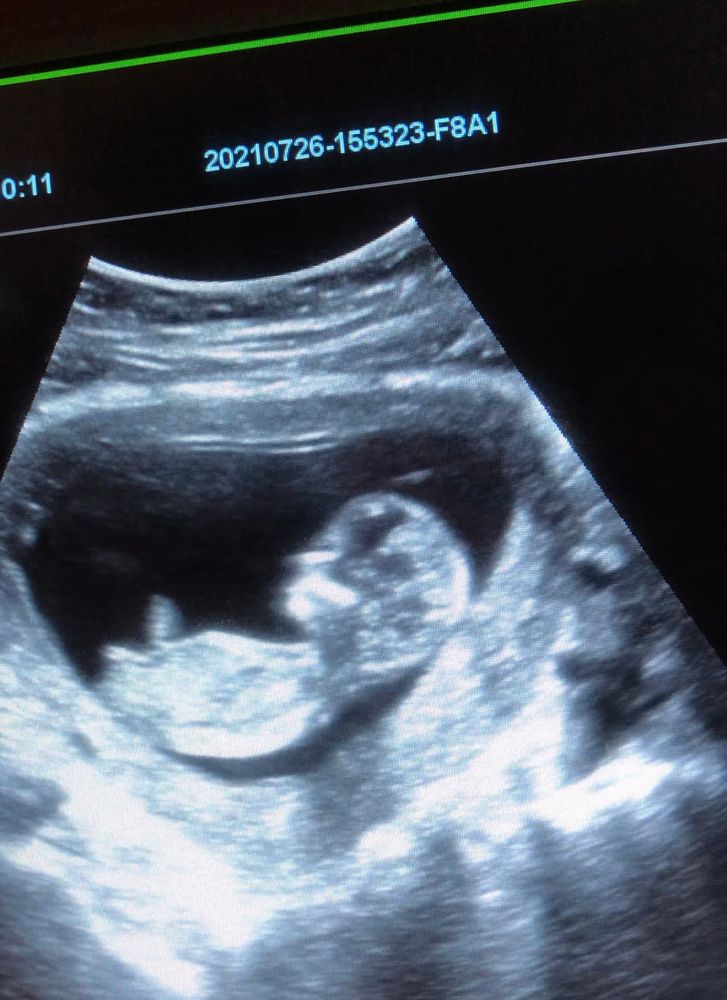

УЗИ, КТГ, доплерСегодня сходила на узи по определению пола, сказали, что будет девчуля,👧 гадания по методу Рамзи и половому бугорку на мне не сработали🤷🏻♀️ Завтра отправлюсь к другому узисту по показаниям, кровит с 13 недели. Думаю завтра уж точно будет известно, кто ж у нас в пузике💕

это фото, сделанное сегодня